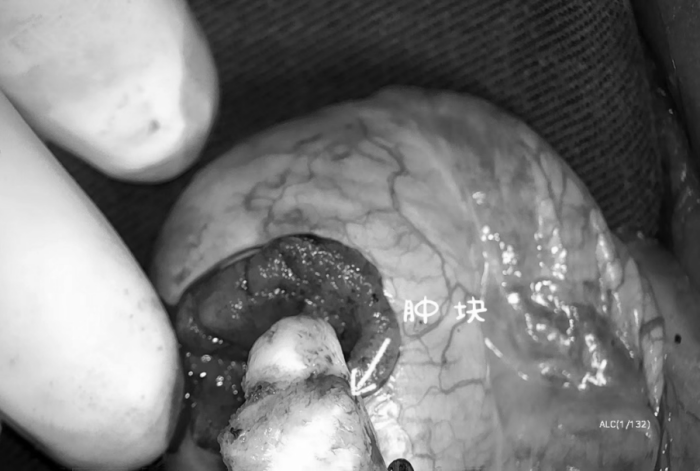

然而,朱劍勇發(fā)現(xiàn)這個(gè)腫瘤長(zhǎng)在睪丸中間,周?chē)泻芏嗌」?,傳統(tǒng)手術(shù)切除,會(huì)導(dǎo)致生精小管缺損,對(duì)今后的生育可能產(chǎn)生影響。

經(jīng)泌尿外科團(tuán)隊(duì)討論后完善手術(shù)方案,決定為小張行“顯微鏡下睪丸腫瘤剜除術(shù)”。手術(shù)中沿著腫塊的邊緣切開(kāi),在顯微鏡的放大作用下,腫塊周?chē)难芎颓?xì)精管清晰可辨,曲細(xì)精管用顯微鑷小心剝離,血管通過(guò)電凝進(jìn)行止血處理,術(shù)中出血很少,腫塊也完整剝出。

術(shù)后第二天小張便順利出院,術(shù)后病理也證實(shí)術(shù)前的判斷,是睪丸錯(cuò)構(gòu)瘤。